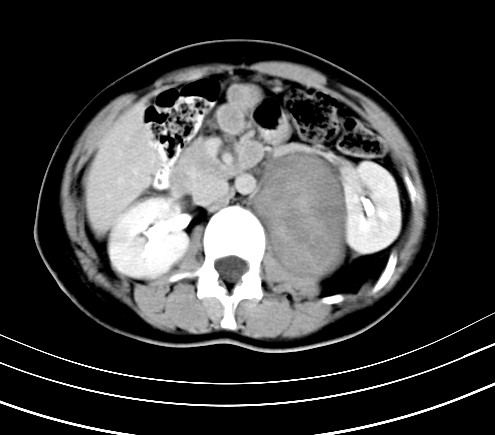

腹部平扫